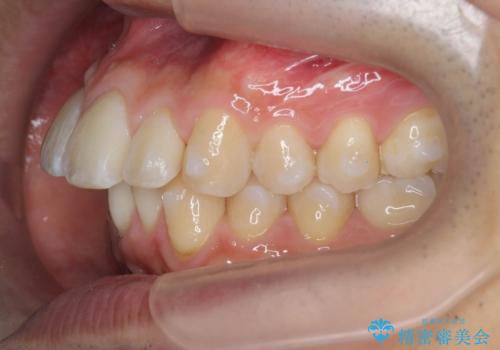

マウスピース矯正で前歯の角度、ガタガタをきれいに

- 突き出た前歯の角度、歯ブラシのしづらい前歯のがたつきの改善を希望され来院されました。

4本の小臼歯を抜きワイヤー矯正治療、下顎前歯を1本抜去しマウスピース治療のメリットデメリットを検討・相談し、より歯を抜く本数の少ないマウスピース矯正を行うこととなりました。

下顎の前歯は1本だけ抜去せざるをえませんでしたが、4本の小臼歯抜去とマルチブラケット矯正を回避することができ、治療結果・過程に満足いただくことができました。